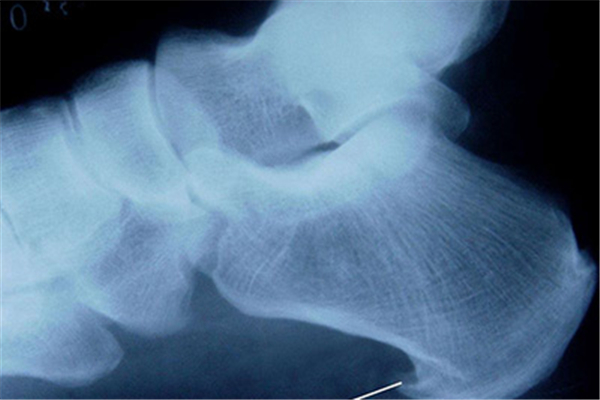

骨質(zhì)增生雖說先開始的時候不會有什么癥狀,但是在后面的時候就會有疼痛的現(xiàn)象,這骨質(zhì)增生是因為缺什么營養(yǎng)所引起的嗎?骨質(zhì)增生是缺鈣嗎?

骨質(zhì)增生并不是因為缺鈣所引起的,骨質(zhì)疏松卻和鈣有一定的關(guān)系。骨質(zhì)增生主要是由于周圍肌筋膜軟組織損傷而導(dǎo)致,由于基金膜損傷或者鈣化而導(dǎo)致局部牽引,長時間對骨膜產(chǎn)生牽引而導(dǎo)致骨質(zhì)增生或者是骨刺。

骨質(zhì)增生是一種影像學(xué)的表現(xiàn)出,是骨關(guān)節(jié)退變致使,通常骨關(guān)節(jié)退變后局部穩(wěn)定性上升,反反復(fù)復(fù)的異常刺激致使局部自身的修補反映,再次出現(xiàn)骨質(zhì)增生,常再次發(fā)生于四肢的關(guān)節(jié)部位,和脊柱部位,病發(fā)早期可無明顯癥狀,當(dāng)炎癥明顯時有疼痛不適癥狀,口服非甾體抗炎藥救治,可以紓解疼痛,壓制纖維化的擴張。需要強調(diào)的是注意多吃一些富含鈣質(zhì)和蛋白質(zhì)的食物,能夠促進骨頭的生長和愈合。